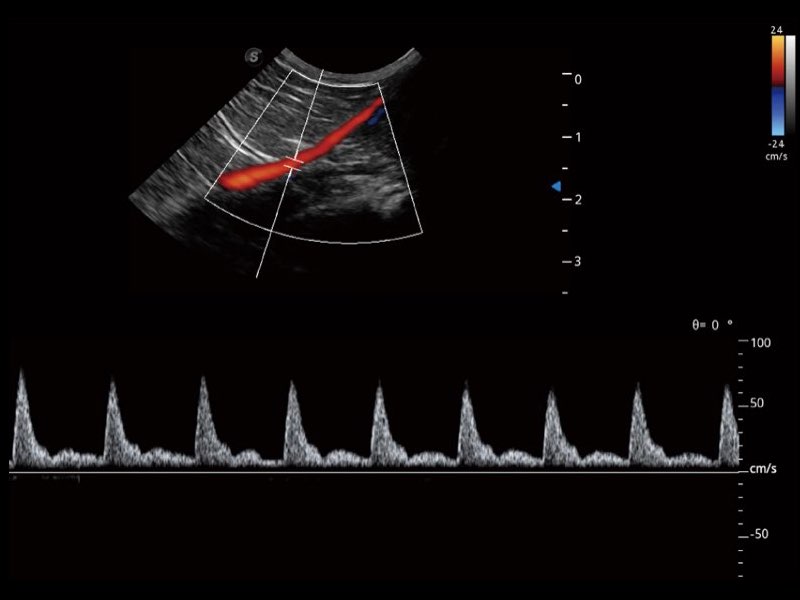

Przy pracach nad aparatem ProPet 60 uwzględniono najważniejsze preferencje i potrzeby weterynarzy, oferując finalnie przystępne cenowo i odpowiednio wyważone połączenie znakomitej precyzji klinicznej, zwiększonej wydajności i przemyślanego przebiegu pracy, niezastąpione w codziennej praktyce weterynaryjnej. Dzięki dostępowi do pełnej gamy głowic HD rozwiązanie to spełnia wszystkie potrzeby w zakresie obrazowania, umożliwiając wykonywanie badań jamy brzusznej, małych narządów, ortopedycznych, badań podczas rozrodu, a nawet badań serca i klatki piersiowej, a to wszystko przy doskonałym stosunku jakości do ceny.